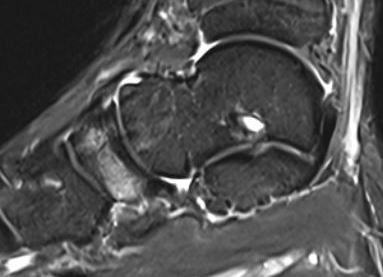

MRI

Minimally displaced navicular stress fracture